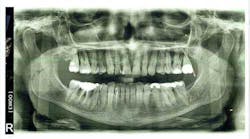

Figure 2a: Panoramic x-ray

Because of my severe bone-loss condition (figures 2 and 2a), I was advised by many offices that my treatment should consist of: extraction, bone grafts, sinus lifts, implants, and crowns. This was very expensive and, I felt, very invasive. I was reluctant, preferring to try to keep my teeth.